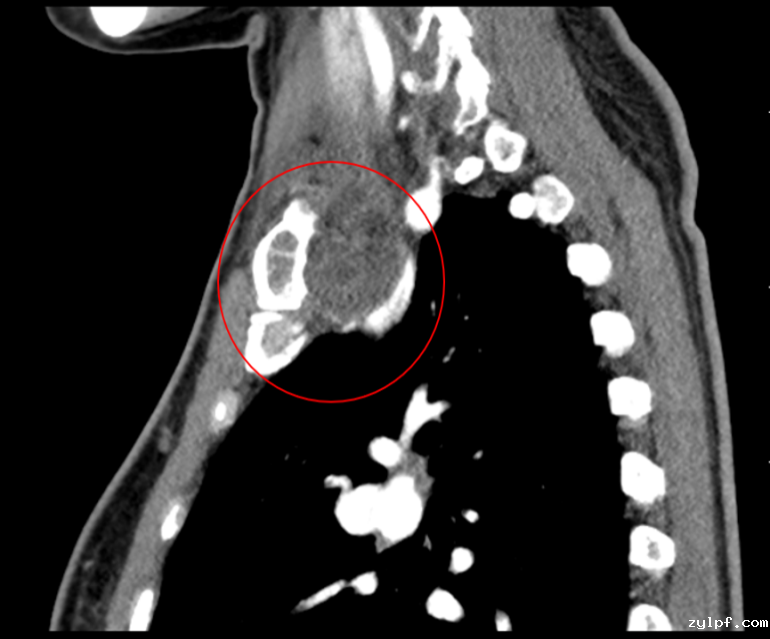

患者50岁女性,因体检发现右锁骨肿物10余天来诊。入院后X光片示右锁骨胸骨端膨大,密度减低,CT及MRI检查提示右侧锁骨局部骨性凸起伴周围肿块形成,考虑右锁骨胸骨端软骨肉瘤。

图片 2.png图片 3.png